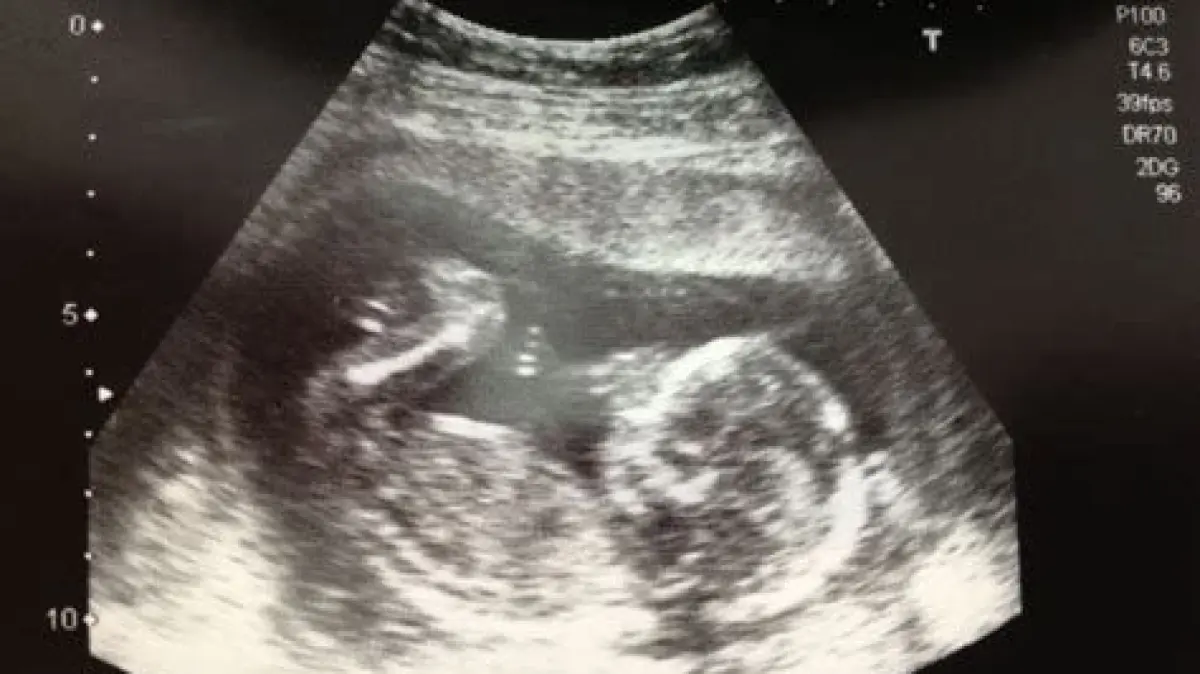

Penting diperhatikan bahwa setiap kehamilan itu unik. Jika Anda belum merasakan gerakan janin pada usia kehamilan 20 minggu, jangan panik. Konsultasikan dengan dokter atau bidan untuk memastikan semuanya baik-baik saja. Dokter mungkin akan melakukan USG untuk memeriksa kondisi janin.